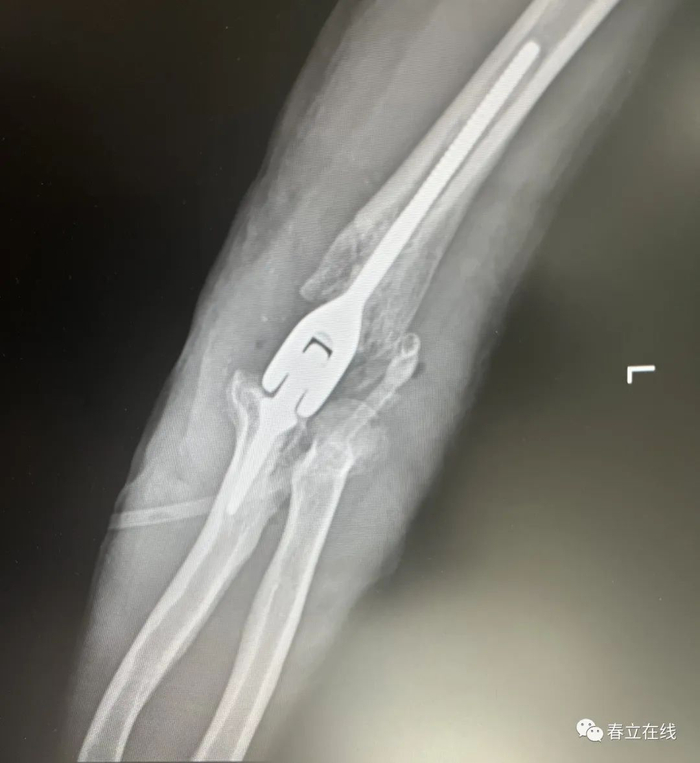

【行X线检查提示】1、左肱骨下端粉碎性骨折;2、左侧尺骨未见异常。

【初步诊断】1、开放性多发性前臂骨折;2、开放性肱骨骨折。